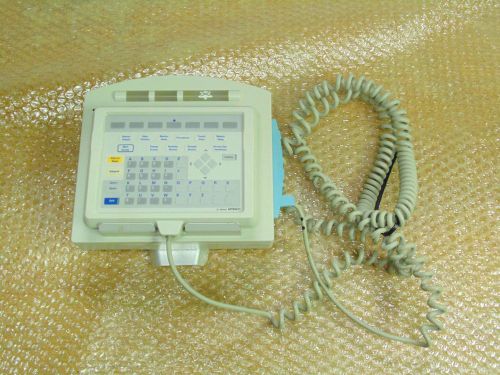

Philips Agilent Remote Alarm M1109A & Handheld Keypad M1106C